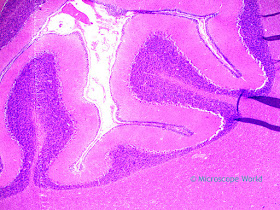

Cerebellum c.s. under the microscope at 40x. |